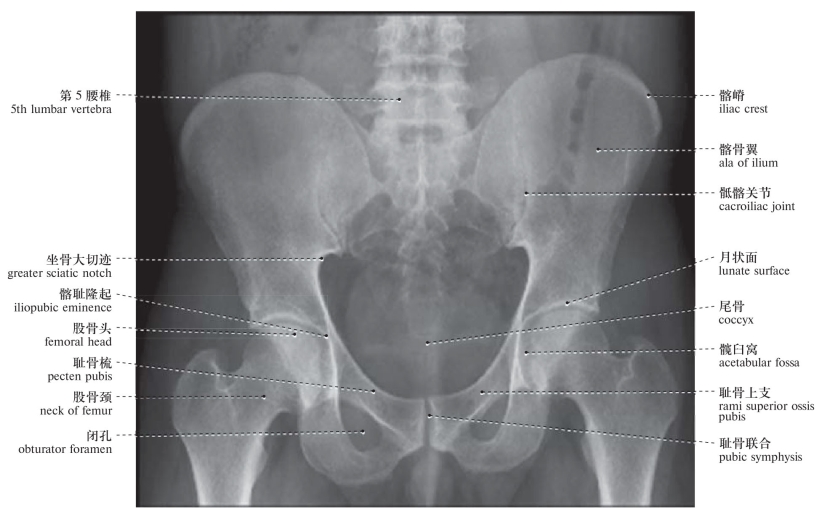

图37 男性骨盆X线像(前后位)

Radiograph of the male pelvis (anteroposterior view)